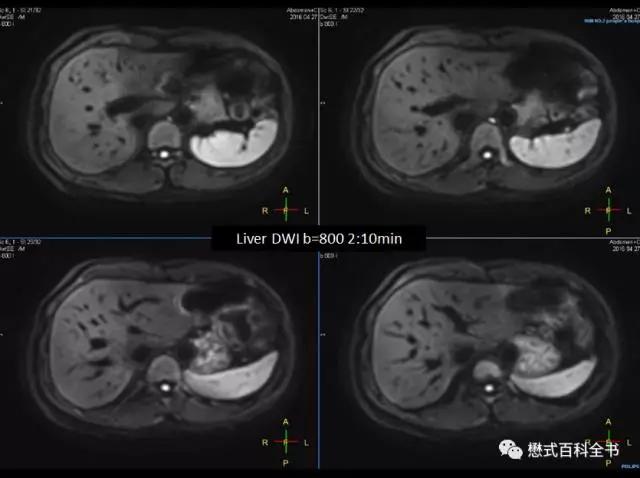

图13:腹部DWI,B值800,扫描时间2分10秒,呼吸触发,图像清晰。

体部中,在腹部中,目前,国内大部分医院,达成的共识是:

1.5T中,腹部使用两个或3个B值,最高B值为600,中间可以设置一个20或50的B值。即3个B值:0,20(50),600;

3.0T中,腹部常规使用两个或三个B值,最高B值800,中间可以设置一个20或50的B值。即3个B值:0,20(50),800。